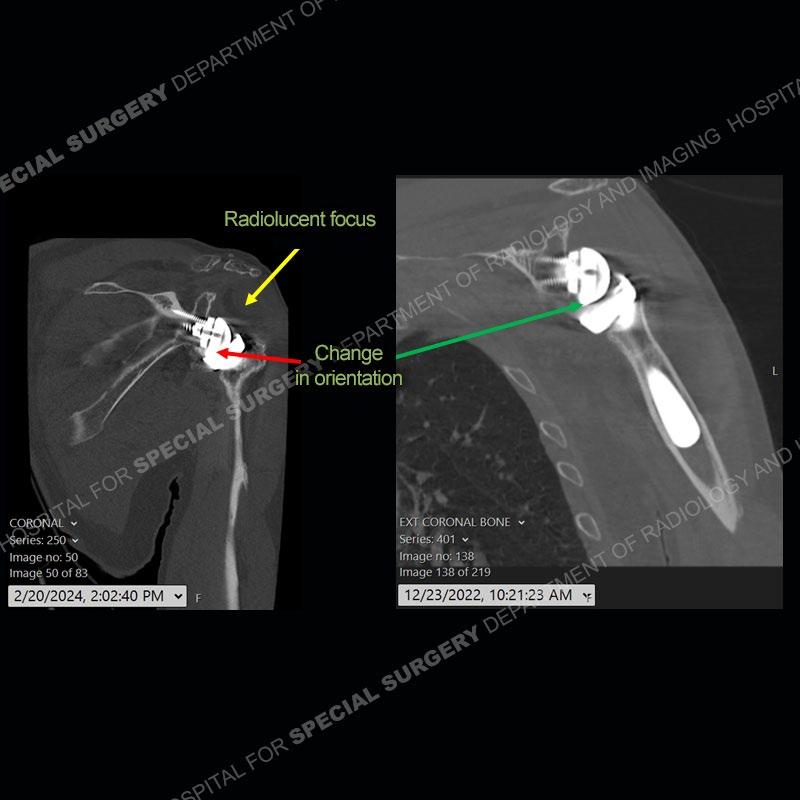

When comparing the radiographs, there is a slight change in the alignment in the components of the prosthesis. On the current radiographs, a radiolucent, crescentic focus is present at the level of the glenoid. When comparing the CT exams, there is a change at the alignment of the glenosphere and the humeral component and now a direct apposition of the components. On the current CT, the radiolucent, crescentic focus is again identified.

If comparison radiographs are present, subtle changes can be made more apparent. Instead of a space between the glenosphere and the humeral tray, there is a direct contact, and there may be an overall change in the alignment at the articulation. The displaced, radiolucent polyethylene liner depending on location can be seen on the radiographs, as in this case. At times, the liner may overlie other structures making identification very difficult on radiographs, but it should almost always be able to be identified on CT (as shown in this example as well). This patient is scheduled for revision procedure.